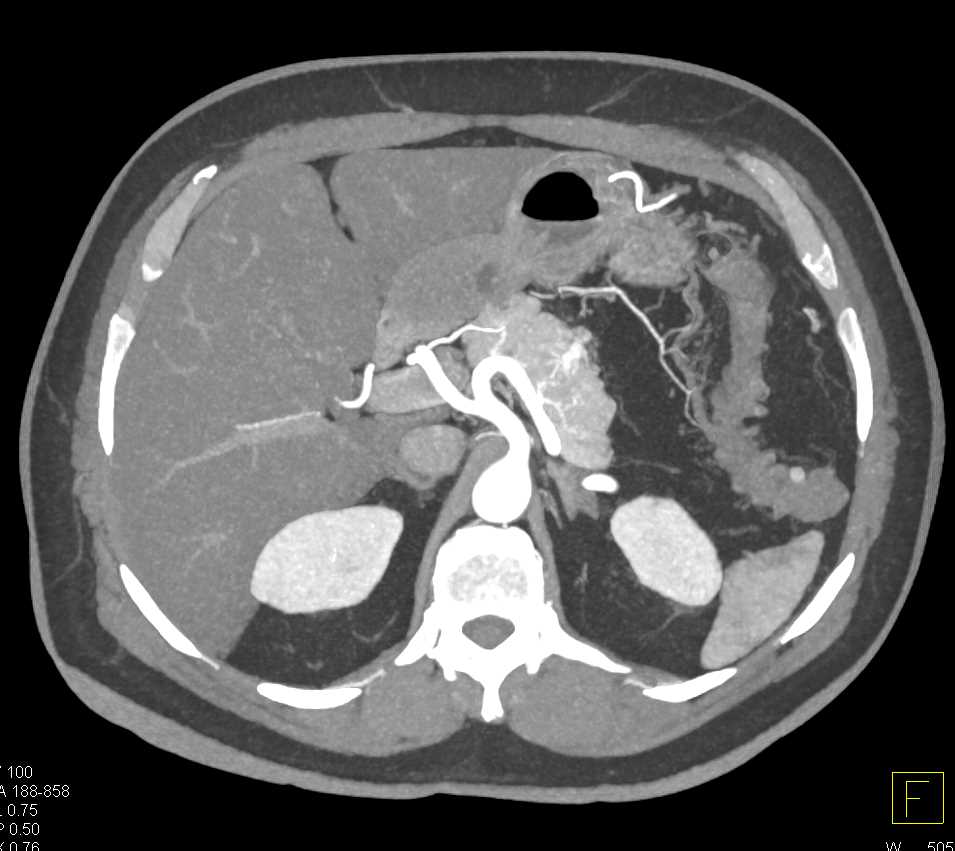

Carcinoma Body of the Pancreas